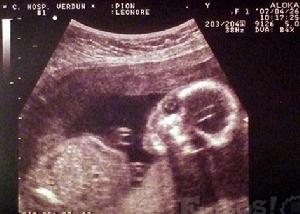

在臨床套用方面,B超可以清晰地顯示各臟器及周圍器官的各種斷面像,由於圖像富於實體感,接近於解剖的真實結構,所以套用超聲可以早期明確診斷。例如:眼科診斷非金屬異物時,在玻璃體混濁的情況下,可顯示視網膜及球後病變。對心臟的先天性心臟病、風濕性心臟病、粘液病的非浸入探測有特異性,可代替大部分心導管檢查。它亦可用於小血管的通斷、血流方向、速度的測定可廣泛套用。早期發現肝占位性病變的檢出已達到1厘米水平。還可清楚地顯示膽囊總膽管、肝管、肝外膽管、胰腺、腎上腺、前列腺等等。B超檢查能檢出有否占位性病變,尤其對積液與囊腫的物理定性和數量、體積等相當準確。對各種管腔內結石的檢出率高出傳統的檢查法。對產科更解決了過去許多難以檢出的疑難問題。如既能對胎盤定位、羊水測量,又能對單胎多胎、胎兒發育情況及有否畸形和葡萄胎等作出早期診斷。

2、了解胎兒生長發育情況:B超既可以測量胎兒的各個部位,如胎頭大小、胎臀長度,也可以用於在早期妊娠來測定胎兒的具體懷孕時間(醫學上叫做孕周),測定胎頭的雙頂徑、頭圍、腹圍及胎兒股骨的長度等,這些數據可以判斷胎兒的生長發育情況。

4、用於產前疾病診斷:B超可以有效發現胎兒畸形,一般在妊娠18-20周檢查可篩查胎兒有無畸形,為早期診斷早期採取措施提供依據。一旦發現胎兒畸形,早期容易終止妊娠,如消化道畸形,神經管畸形,如無腦兒、脊柱裂等等,都可以及時採取流產、引產措施。

第1次B超檢查應在妊娠12~16周:這時做B超檢查可確定懷的是單胎還是多胎,並可測量胎兒的大小及其發育情況

第2次B超檢查應在妊娠20~25周:懷孕中期的B超檢查可幫助準媽媽了解胎兒的生長發育情況,還能對胎兒的位置及羊水量有進一步的了解。還可以早期發現胎兒畸形,如胎兒的肢體畸形、唇齶裂畸形等。